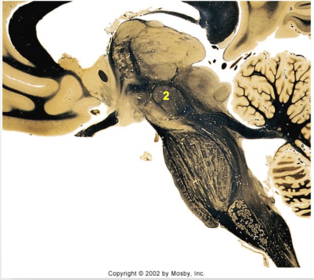

| Head of caudate | |

| Anterior commissure | |

| Thalamus | |

| Substantia nigra | |

| Optic tract | |

| Dentate nucleus | |

| Pons | |

| Longitudinal pontine fibers | |

| Uncus | |

| Superior cerebellar peduncle | |

| Red nucleus | |

| Corticospinal tract (dark) | |

| Pontine nuclei (pale) | |

| Transverse pontine fibers (dark) | |

| Inferior olive | |

| CTT | |

| Medial lemniscus | |

| Nucleus cuneatus | |

| Superior colliculus | |

| Inferior colliculus | |

| Optic nerve | |

| Cerebellum | |

| 4th ventricle | |

| Periaquaductal gray | |

| Dorsal funiculus | |

| MLF | |

| Mammillary body | |

| Pineal body | |

| Posterior commissure | |

| Thalamus |